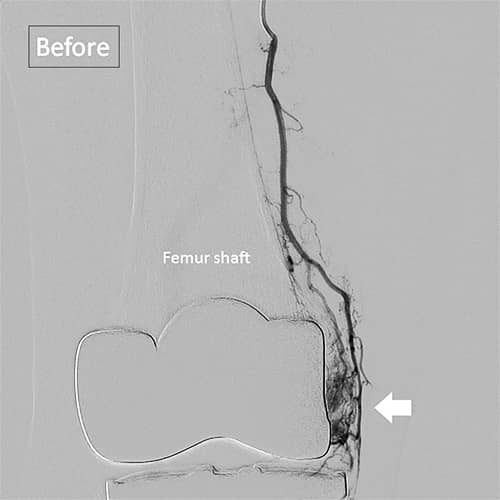

ひざの人工関節を入れた後に痛む・・・その理由は?

[記事提供:オクノクリニック | モヤモヤ血管による慢性痛治療(https://okuno-y-clinic.com)]…